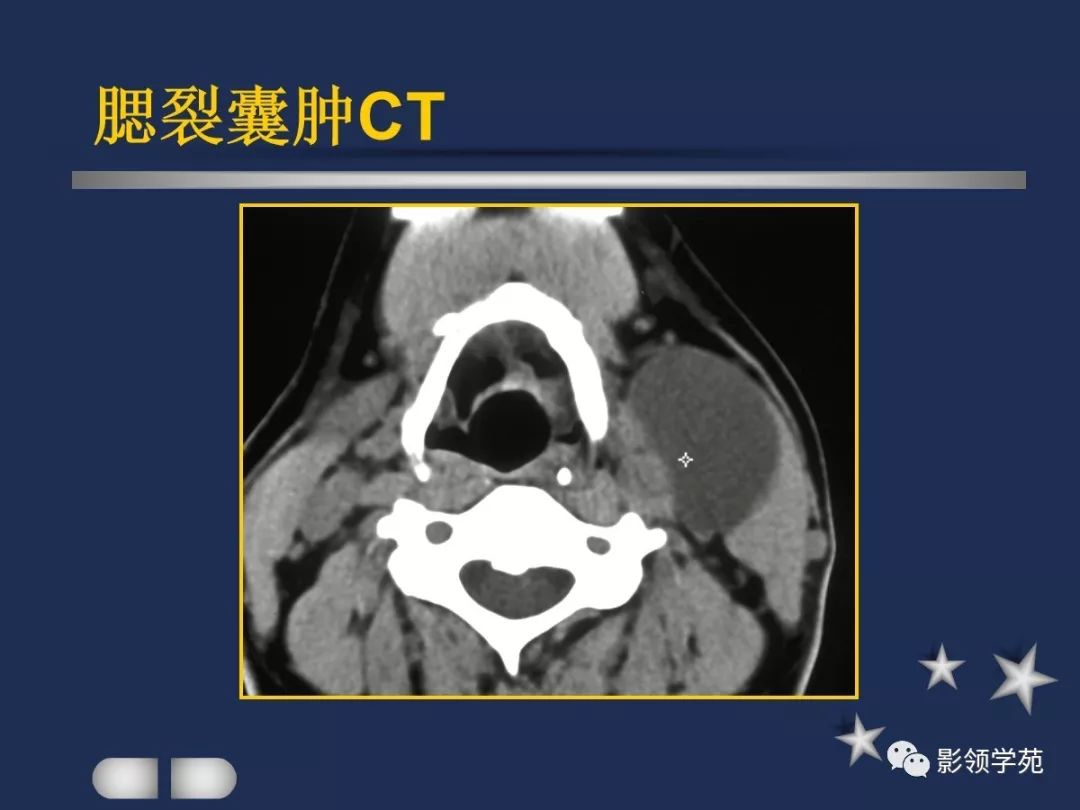

- 腮裂囊肿